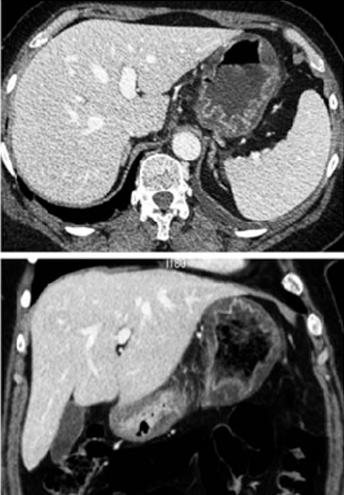

Image TDM en coupe axiale et

dans la paroi de estomac ( coupe TDM coronale ) |

Image radiologique TDM

peritoneale ( peritonite ) |